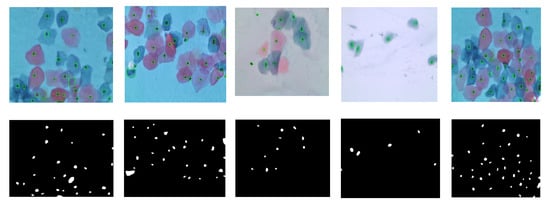

2. Materials and Methods

2.3. Cells Segmentation

2.4. Nuclei and Cytoplasm Segmentation